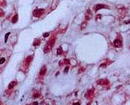

浅表软组织肿瘤指起源于皮肤与深筋膜之间的间叶组织(脂肪、血管、纤维和肌肉等) 良恶性肿瘤的统称, 具有分布广、种类多、形态复杂以及临床表现各异等特点,在日常临床实践中,绝大多数浅表软组织肿瘤为良性, 如何准确诊断和鉴别诊断仍然面临挑战, 中间性或恶性肿瘤相对少见, 若误诊或处理不当, 可导致复发或远处转移。目前浅表软组织肿瘤的主要影像学检查方法包括CT、MRI 及超声检查, 超声检查以其实时、便捷、可重复性、无辐射、高分辨率及能够评估血流动力学等优势,已经成为浅表软组织肿瘤首选的影像学检查方法,尽管在各级医疗机构中浅表软组织超声检查已经非常普遍, 但操作规范、诊断术语、报告书写方面存在较大差异, 诊断技术方面缺乏标准化的管理。为进一步提高我国浅表软组织肿瘤超声诊断的规范化和标准化水平, 由中国抗癌协会肿瘤超声医学专业委员会、中国医学装备协会超声装备技术分会及天津市抗癌协会肿瘤超声医学专业委员会组织国内有关临床、超声、病理专家, 针对浅表软组织肿瘤超声检查常见问题, 经过反复讨论, 参考相关文献,并结合国内专家临床实践, 形成本共识, 旨在促进超声医师更加全面且规范地进行软组织肿瘤的超声检查与评估, 为患者术前评估以及术后随访提供标准化的超声影像评价。 展开